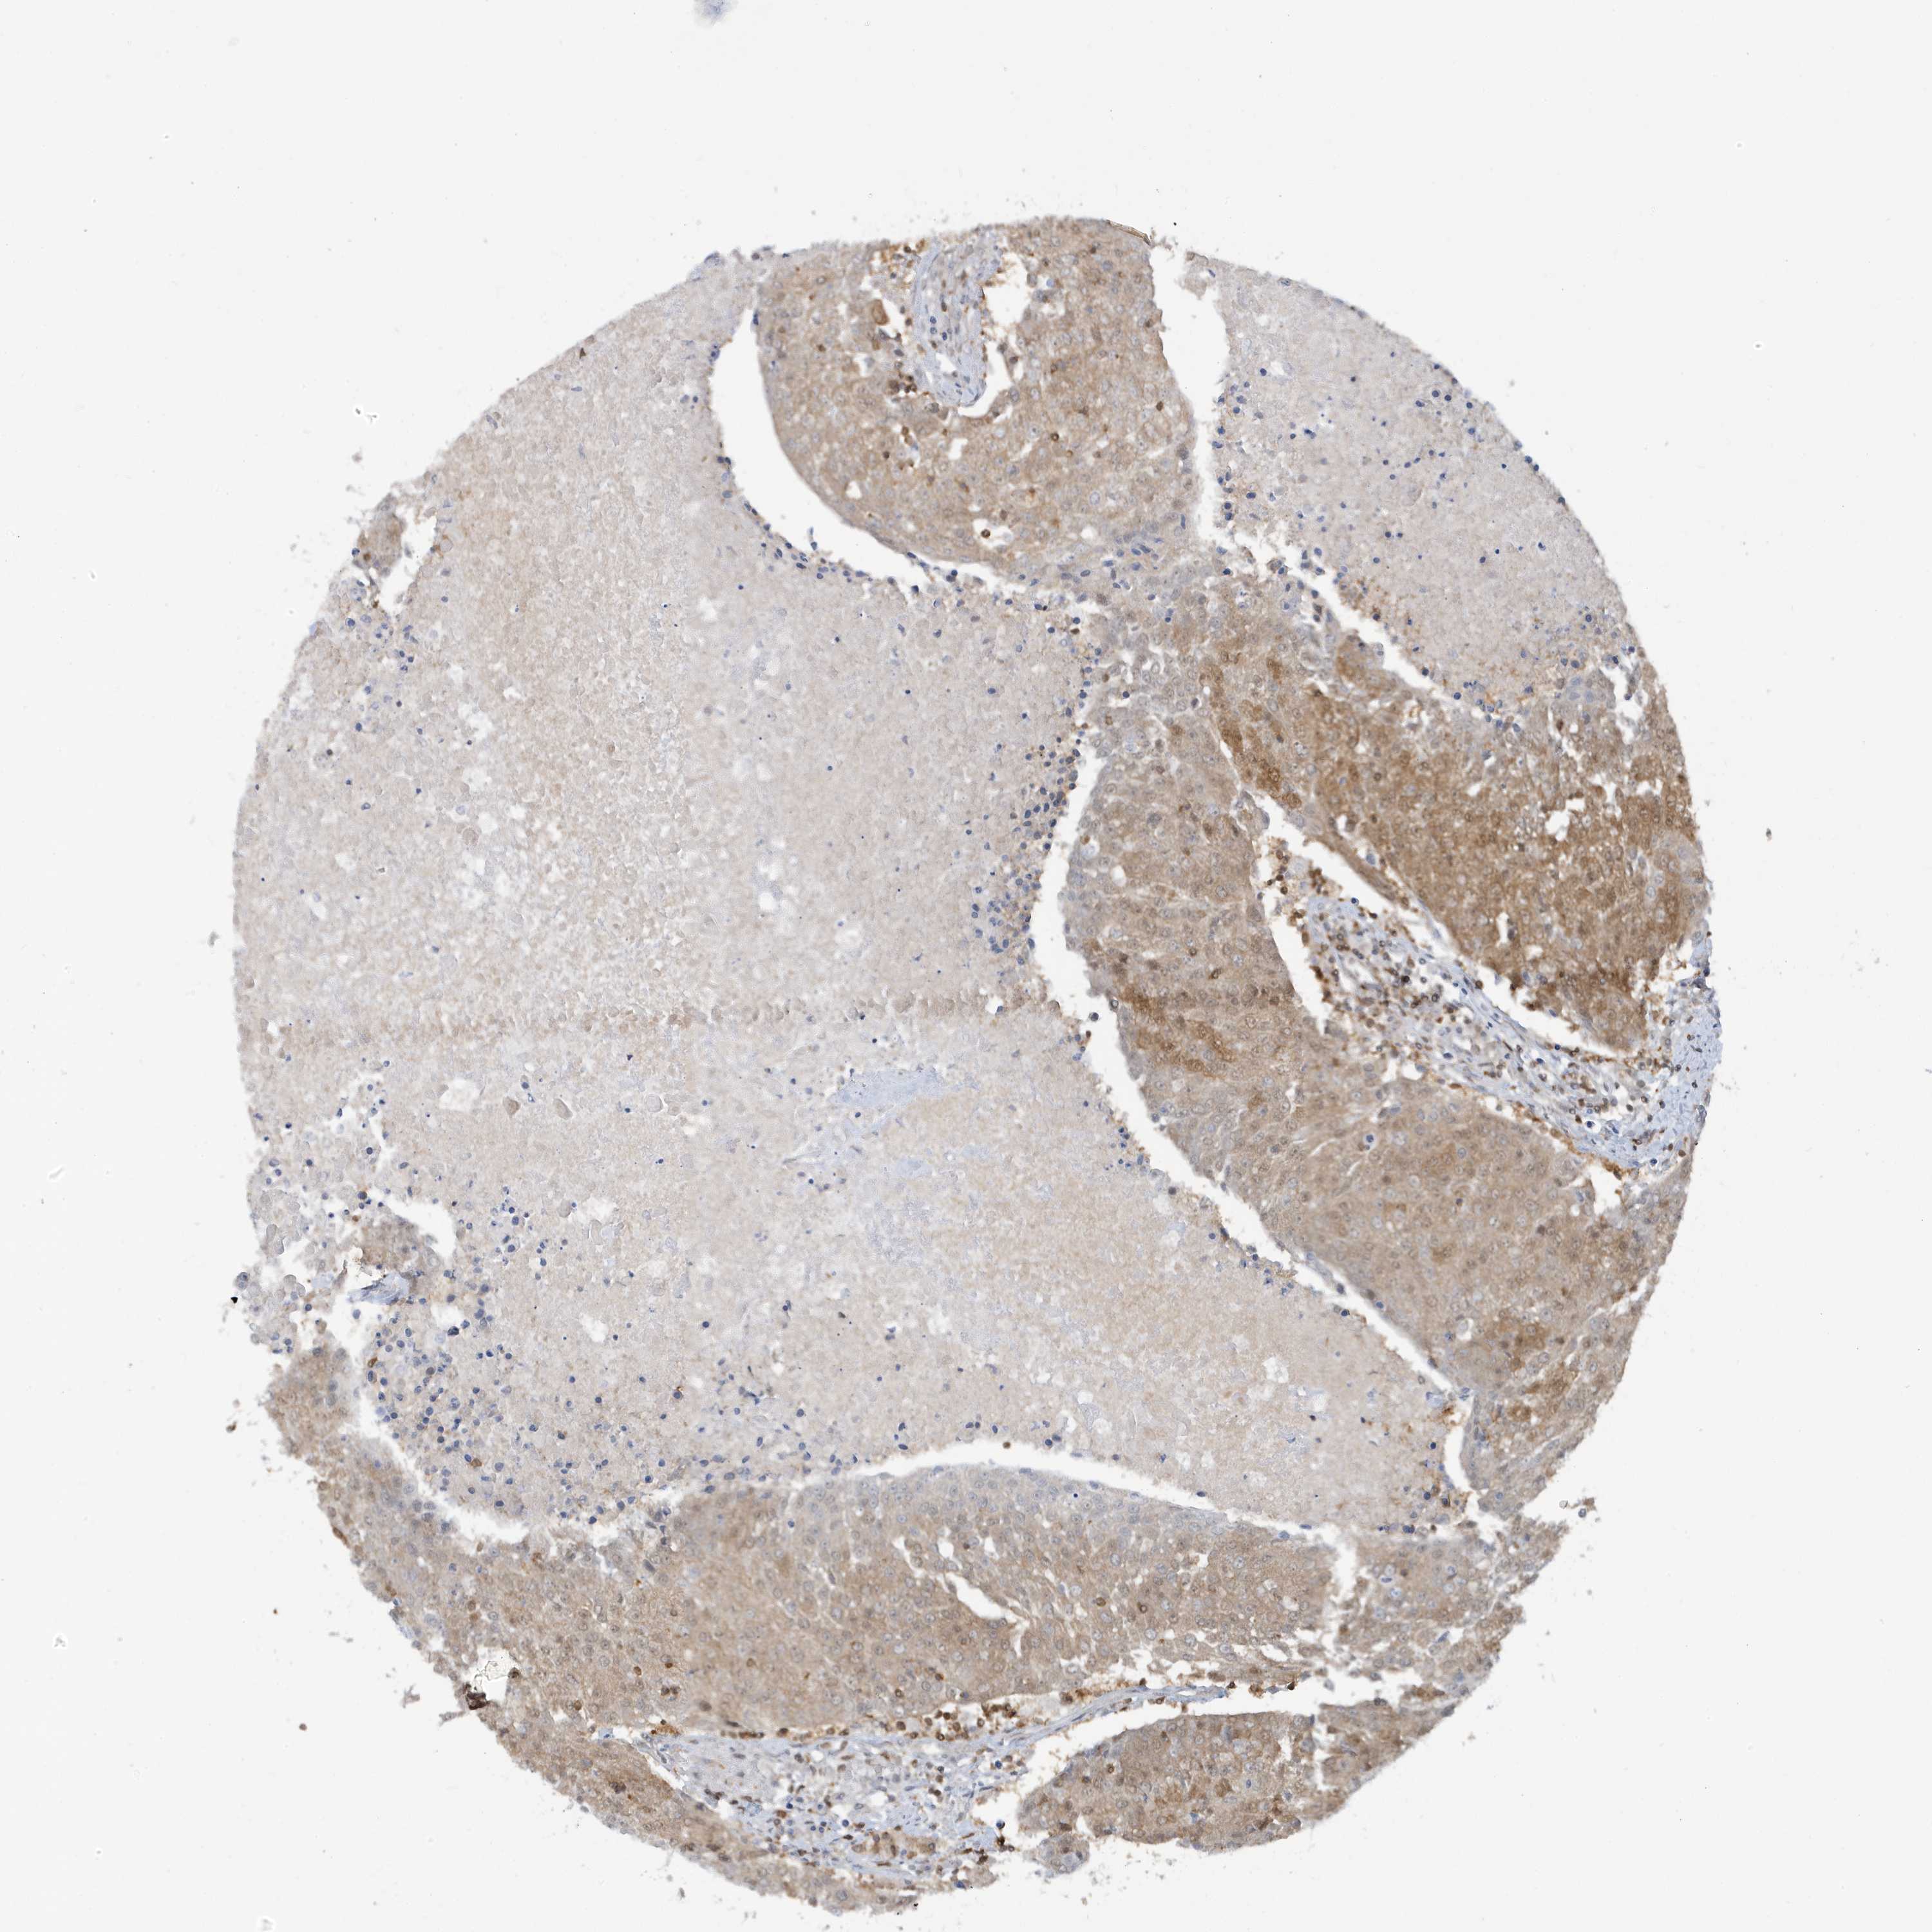

UROTHELIAL CANCER - Protein expressioni

A mouse-over function shows sample information and annotation data. Click on an image to view it in a full screen mode. Samples can be filtered based on level of antibody staining by selecting one or several of the following categories: high, medium, low and not detected. The assay and annotation is described here.

Antibody stainingi

Antibody staining in the annotated cell types in the current human tissue is reported as not detected, low, medium, or high, based on conventional immunohistochemistry profiling in selected tissues. This score is based on the combination of the staining intensity and fraction of stained cells.

Each image is clickable and will lead to virtual microscopy that enables deeper exploration of all samples and also displays staining intensity scores, fraction scores and subcellular localization as well as patient and tissue information for each sample.

Antibody HPA036141

Staining

High

Medium

Low

Not detected

Intensity

Strong

Moderate

Weak

Negative

Quantity

>75%

75%-25%

<25%

None

Location

Nuclear

Cytoplasmic/membranous

Cytoplasmic/membranous,nuclear

Urothelial carcinoma, Low grade

Urothelial carcinoma, High grade